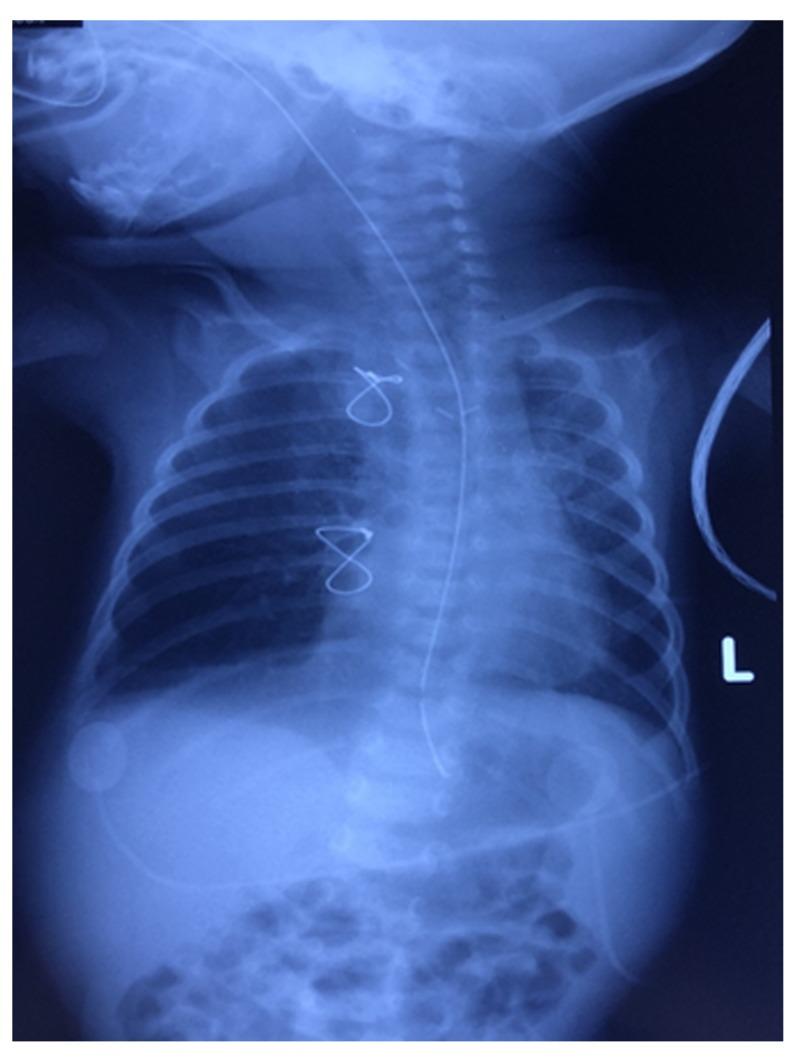

Pulmonary artery sling is a rare cause of neonatal respiratory distress. Most patients with pulmonary artery sling present in early infancy with stridor and signs of respiratory distress. Diagnosis of pulmonary artery sling, like other vascular ring anomalies, can be made using various imaging modalities, and management encompasses urgent surgical repair as a definitive treatment. This is the first paper to report a successfully managed case of an early detected left pulmonary artery sling during the first week of life in a term male patient and to evaluate the diagnostic characteristics in alliance with it. CAse REports (CARE) guidelines were followed for reporting our case. In brief, a case of full-term baby boy was born by normal vaginal delivery and shortly after birth, the baby started to have respiratory distress not improving on O. Chest X-ray revealed right upper lobe atelectasis which persisted despite mechanical ventilation and antibiotics. A thoracic CT scan showed developmental malformation of left main pulmonary artery, confirming the diagnosis of "left pulmonary artery sling." The baby was immediately operated. One week later, chest X-ray showed gradual improvement and the baby was discharged home with no postoperative complications. Hence, we suggest that pulmonary artery sling should be suspected in any neonate with respiratory distress and unilateral lung field opacification. The fact that there are only very few reports on this disease raises a need to establish and implement well-defined guidelines and criteria for early diagnosis and management of pulmonary artery sling among newborns.